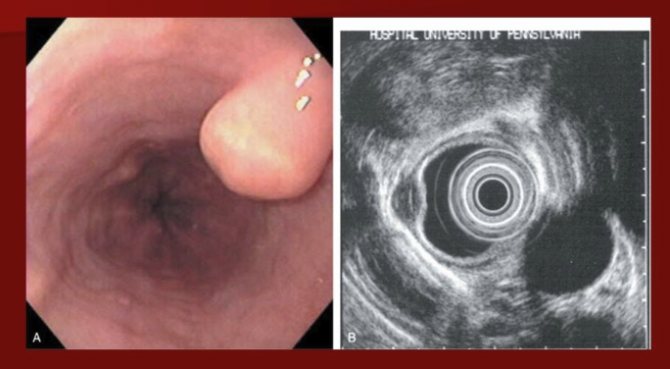

При визуальном осмотре врач не диагностирует наличие заболевания. Прежде чем назначить продуктивное лечение, проводится диагностика с использованием специальных инструментов. Опухоль пищевода можно быть выявлена при рентгенографии с контрастным веществом (барий). Раствор обволакивает орган, на снимке просматриваются нарушения в нормальном строении.

Рентген помогает визуально определить степень сужения пищевода, выявить любые изменения толщины стенки либо наличие язвенных ран.

Благодаря эндоскопу врач изучает, имеет ли стенка наличие спазмов или опухоли. Указанная методика обследования помогает выявить стадию онкологического процесса, присутствие либо отсутствие метастазов в лимфатических узлах и органов расположенных рядом.

С помощью УЗИ фиксируются точные размеры новообразования и вторичные образования, если такие имеются.